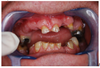

c) Intra buccal :

. Perte importante de la Dimension Verticale, avec usure du 2/3 de la hauteur coronaire des Incisives centrales Supérieures. Affaissement de la hauteur des dents.

. Edentation encastrée et présence d’autres dents réduites à l’état de racines

. Faible ouverture buccale : largeur 1 doigt et demi

. Claquement ATM léger du côté G à l’ouverture

. Absence de la vraie mastication

Rehaussement occlusal progressif de 1,3 cm, avec la réalisation de mordu physiologique, en RC, pour retrouver la hauteur physiologique équilibré naturelle du patient + réalisation de prothèses amovible partielle supérieure et inférieure en Flexite + reconstitution coronaire des dents restantes pour reconstruire du Guidage Antérieur+Calage Postérieur.

Un meilleur sommeil et une audition de meilleure qualité étaient récupérés par la suite progressivement. L’ouverture buccale devenue satisfaite avec une hauteur égale à la largeur de 2 doigts et demi.